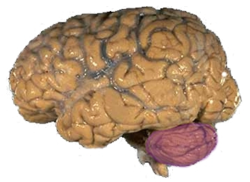

| Figure 1a: A human brain, with the cerebellum in purple. | ||

The cerebellum is located in the inferior posterior portion of the head (the hindbrain), directly dorsal to the pons, and inferior to the occipital lobe (Figs. 1 and 3). Because of its large number of tiny granule cells, the cerebellum contains more than 50% of all neurons in the brain, but it only takes up 10% of total brain volume. The cerebellum receives nearly 200 million input fibers; in contrast, the optic nerve is composed of a mere one million fibers.